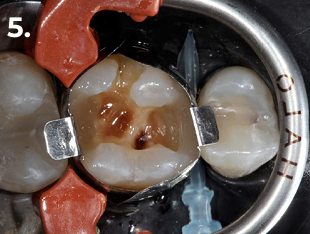

La procedura è stata eseguita in isolamento assoluto, utilizzando il sistema di matrici sezionali HALO™.

Fig. 5 Formazione della parete distale per convertire la cavità in una preparazione di Classe I